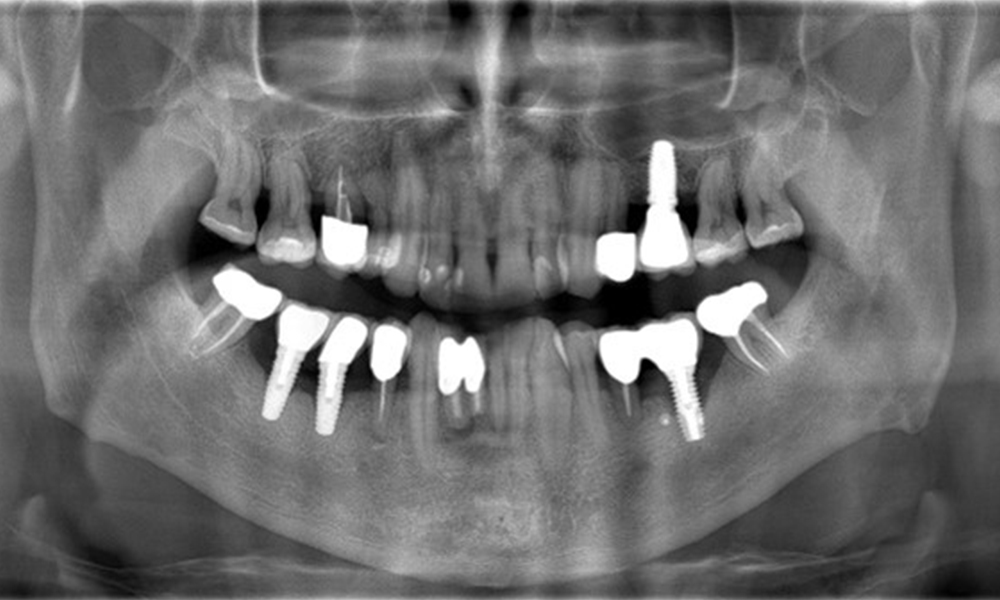

Ein 52-jähriger Patient stellt sich zur Präventionssitzung vor. Der Patient hat keine Allgemeinerkrankungen und nimmt keine Medikamente ein. Er hat verschiedene zahnärztliche Versorgungen und zudem zwei aktive kariöse Läsionen. Außerdem verfügt der Patient über vier Implantate (2., 3. und 4. Quadrant). Es zeigt sich eine parodontale Vorerkrankung (Stadium IV, Grad B). Derzeit herrschen stabile parodontale Verhältnisse, lediglich am Implantat regio 36 zeigen sich Sondierungstiefen (ST) von 5 mm. Zudem lässt sich eine Gingivitis feststellen.

Der Patient zeigt keine besonderen anamnestischen Risikofaktoren mit spezifischen zahnmedizinischen Auswirkungen. Daher ist der aus der Mundgesundheit ermittelte Bedarf maßgebend. Hierbei zeigt sich am Implantat im 3. Quadranten ST von 5 mm und im Röntgenbild eine Zunahme des Knochenverlustes. Der Patient hat zudem eine aktuell stabile parodontale Vorerkrankung und zwei aktive initialkariöse Läsionen.